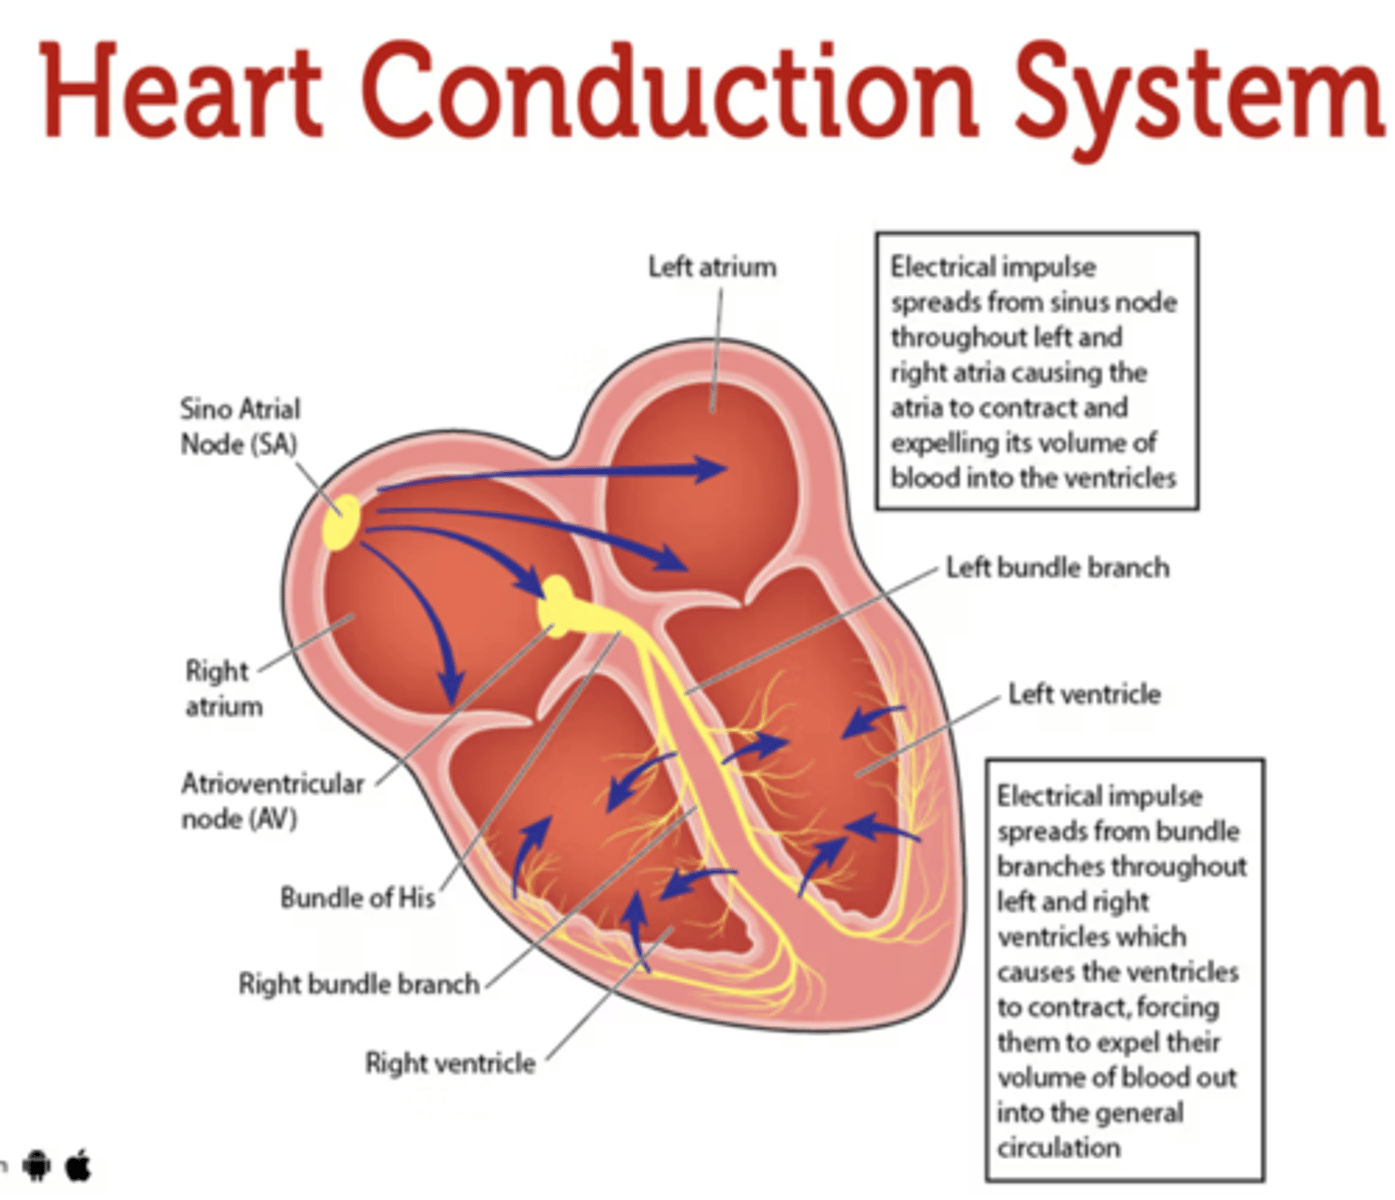

What allows the heart to contract by itself?

The heart possesses a specialized conduction system that gives it the autonomous capacity to contract, allowing it to pump by itself in a correct buffer.

What are the two conduction nodes of the heart conduction system?

. SA node (sinoatrial node)

. AV node (atrioventicular node)

What is the function of the sinoatrial (SA) node?

Pacemaker of the heart

Where is initiated the contraction of the SA node?

SVC (Superior Vena Cava)

passing through the atrium to the AV node

Where is the SA located?

upper wall of the right atrium,

at the junction where the superior vena cava enters

Where is the atrioventricular (AV) node located, and what follows it?

At the level of the atrioventricular septum,

AV node is followed by?

Bundle of Hiss that divides into two branches

Where does Bundle of Hiss ends?

Purkninje fibers

Describe the propagation of waves in the conduction system ?

. SA node sends the initial wave

Passes through the walls of the atria

. Ends at the AV node in the AV septum

. Travels along the Bundle of His

. Reaches Purkinje fibers in the walls of the ventricles

What role does the moderator band play in the conduction system?

Allows the wave to reach the papillary muscles, inducing their contraction simultaneously with that of the ventricles.

REMEMBER: PAPILLARY MUSCLES ACT THROUGH THE CHORDAE TENDINAE TO CONTROL THE TRICUSPID AND MITRAL VALVES.

What is the significance of the Bundle of His in heart conduction?

Branching to the right and left to ensure coordinated contraction of the ventricles.

What are the Purkinje fibers, and what is their function?

specialized conductive fibers in the walls of the ventricles that

facilitate rapid transmission of electrical impulses,

ensuring efficient and synchronized ventricular contraction.

How does the AV node contribute to heart rhythm?

Delays the electrical impulse from the SA node,

ensuring that the atria contract fully to transfer blood to the

ventricles before the ventricles contract.